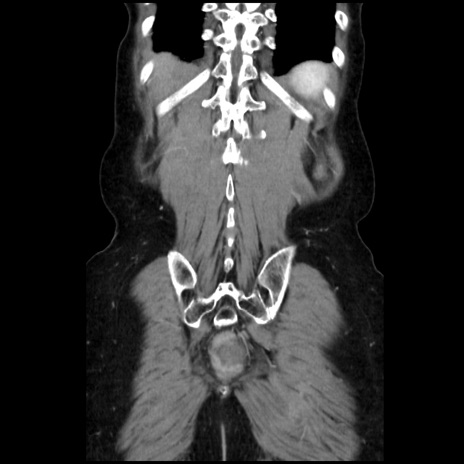

症例32(冠状断像)

【症例】40歳代 女性

【主訴】上腹部痛、嘔気・嘔吐

【現病歴】約9時間前頃から急に上腹部痛、嘔気、嘔吐が出現。改善しないため救急要請。

【既往歴】子宮頚癌(広汎子宮全摘術、放射線療法)、腸閉塞

【身体所見】腹部:平坦、軟、腸雑音亢進、上腹部を中心に腹部全体に圧痛あり。

【データ】WBC 8400、CRP 0.03